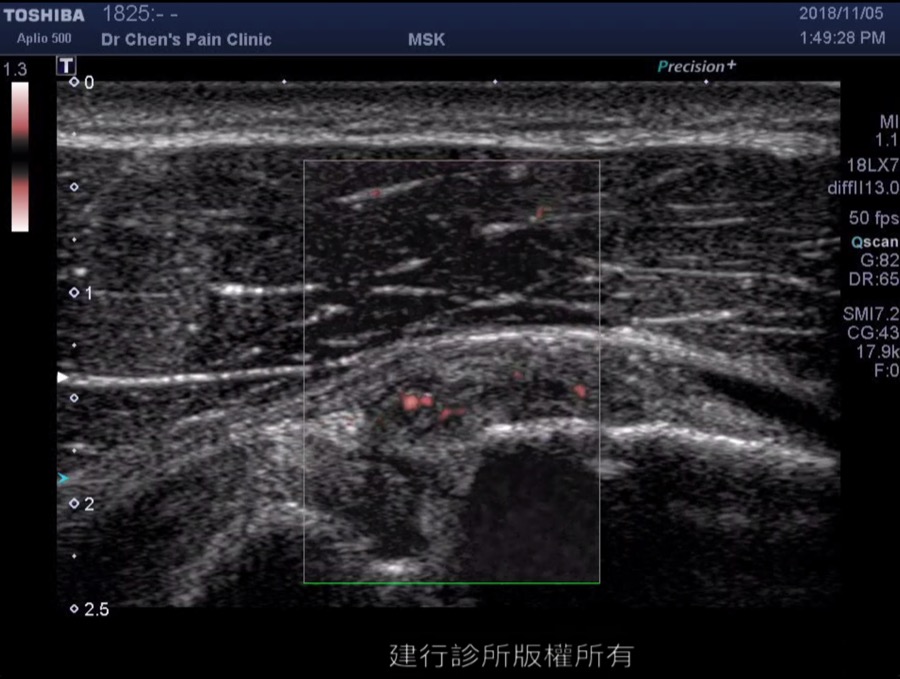

頸椎關節炎的診斷相對簡單,醫師使用觸診技巧找出患者頸部特別疼痛的位置,然後使用超音波確認疼痛位置下方是哪一個頸椎關節發炎。在確認正確的位置之後,可以先